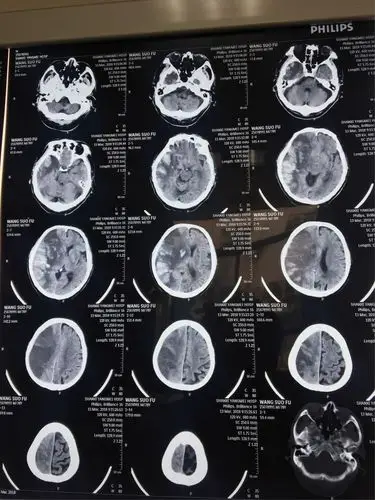

一例脑梗死患者的ct演变及治疗过程

术前ct片

原创颅脑ct片帮忙看看

请问哪位一生可以帮我看看这张脑ct片子有什么问题?